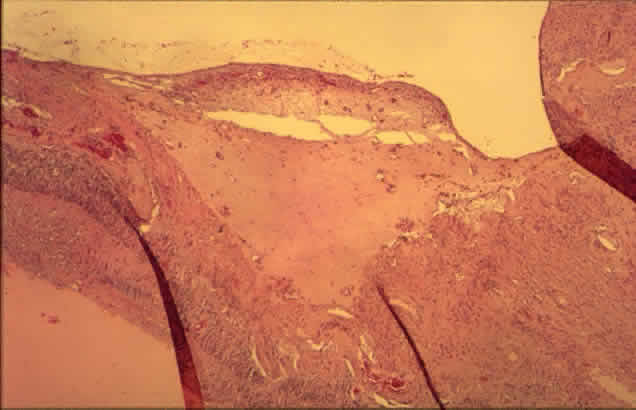

Radiant energy in the visible spectrum passes through the transparent retina and is absorbed by melanin pigment, hemoglobin, or both, depending on the wavelength chosen. The result is a focal scar of the outer retina, or if intense enough, full-thickness retina (Fig. 14).61 Full-thickness scars can cause extensive visual field loss because of obliteration of the nerve fiber layer.20

Fig. 14. Low-power view of panretinal photocoagulation. Normal retina is to the extreme right. Centrally there are areas of outer retinal loss (center arrows), and to the extreme left (single arrow) is an area of full-thickness retinal loss with migrated pigment epithelium. (H&E, × 19.5)